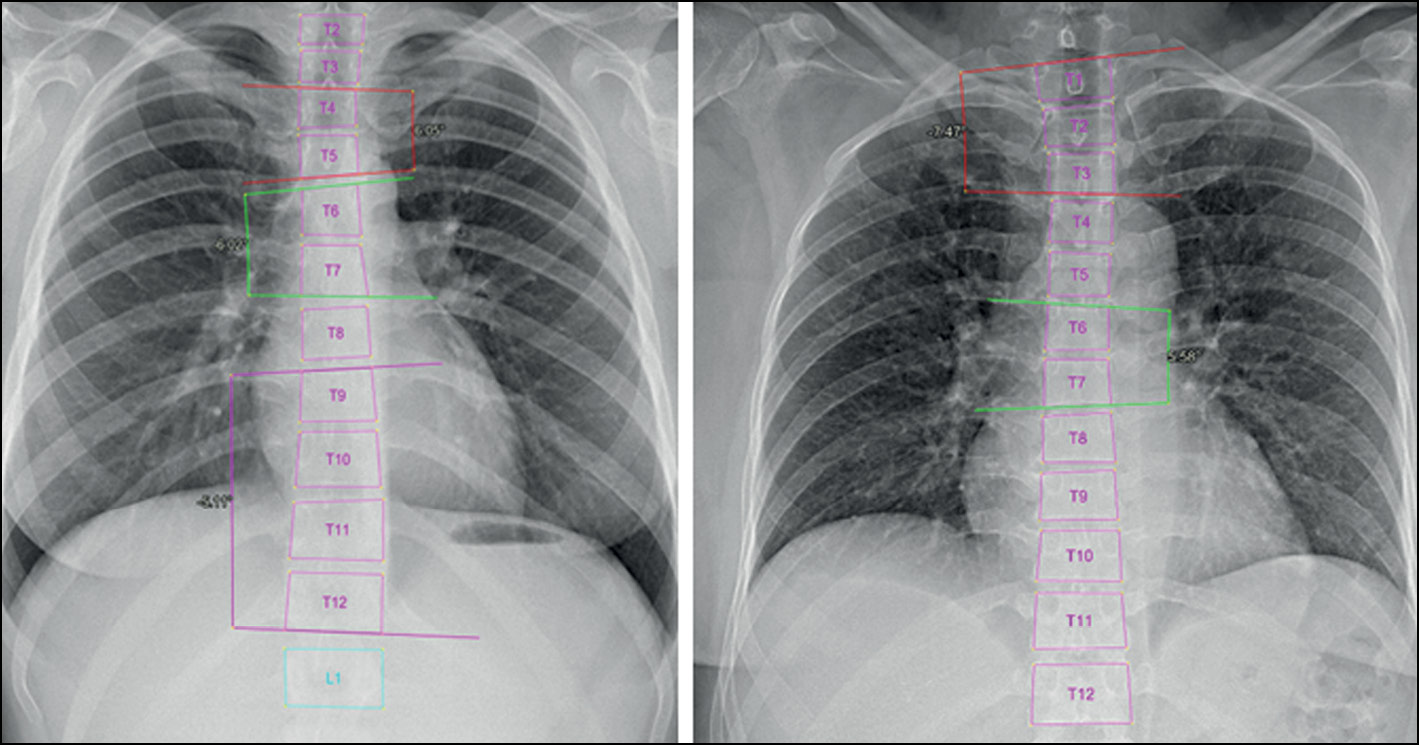

In addition, when using the program, the radiologist can change vertebral markings made by the system automatically. This is very essential to overcome any errors in vertebral markings that can cause a false final result. Further analysis of the results showed that the inaccurate marking of vertebral bodies and their borders predominantly led to less accurate results of angle measurement and scoliosis grade definition. This was mainly seen when evaluating scoliosis in poor-quality images and CXR images. The borders of the midthoracic vertebrae in CXR images usually are not seen posterior to the mediastinum. Multiple normal CXR images (grade 0, defined by the radiologist) were recognized by the system as grade 1 scoliosis because of detecting an FP curve (proximal or midthoracic curve) (Fig. 5). Other common error was also seen in marking the borders of L5 vertebral body (Fig. 6). The adjacent bony structures (adjacent sacrum and iliac bones) limit the definition of L5 borders, particularly its lower endplate.

Fig. 5. Errors in vertebral markings on radiographs with grade 0 (normal). In CXR images, poor definition of the vertebral borders may lead to false measurements.